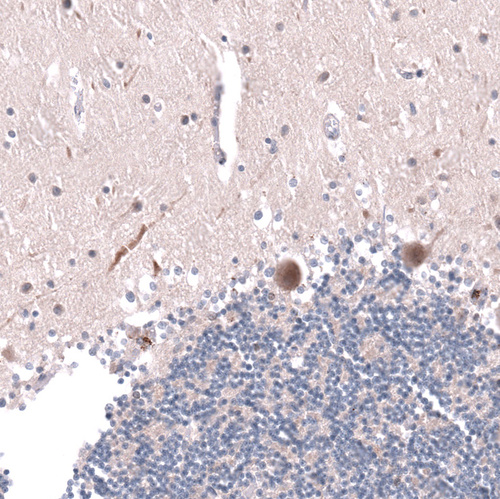

Immunohistochemical staining of human cerebral cortex shows strong nuclear positivity in oligodendrocytes.